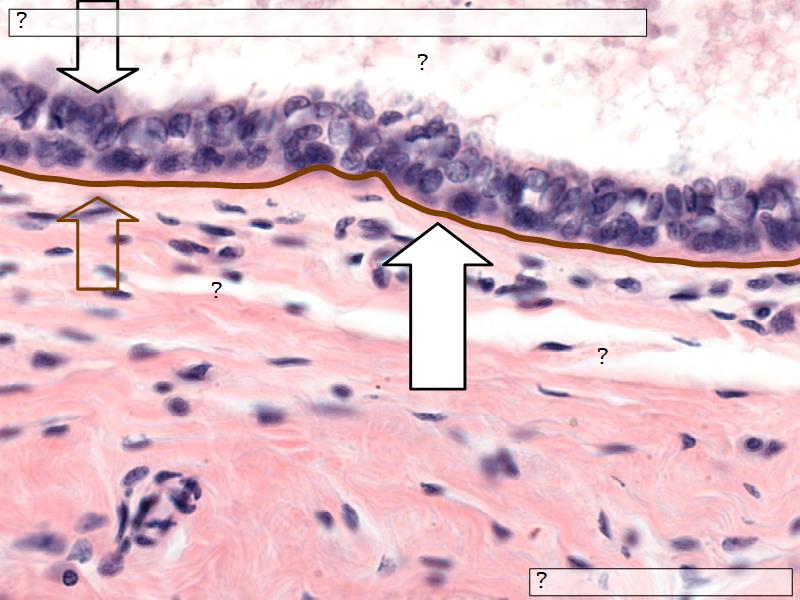

What epithelium are associated with ducts?Q03 - 3

What epithelium are associated with ducts?

Cuboidal epithelium

Q06: Epithelium

- Is bordered by a ______.

- Rests on a ______.

Q06: Epithelium

- Is bordered by a lumen.

- Rests on a basement membrane.

- Lactiferous ducts

- Stratified cuboidal

- Basal lamina

- Separate epithelial components from stroma